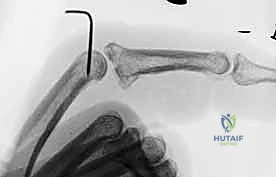

3. Confirming the Blocking Effect and Stability

This is a critical step, fellows. The pin must effectively block hyperextension without restricting necessary flexion.

- Test Extension Block: Gently extend the PIP joint. The middle phalanx should come to a hard stop against the K-wire, preventing full extension and dorsal subluxation. The exact angle of allowed extension will depend on the stability required, typically allowing 20-30 degrees of extension.

- Test Flexion: Gently flex the PIP joint. It should be able to flex fully to 90 degrees or more without impingement from the K-wire. If flexion is restricted, your pin is likely too long or is tethering the extensor mechanism.

- Fluoroscopic Verification: Confirm the blocking effect and joint congruity in all ranges of motion under fluoroscopy.

- Neurovascular Check: Release the tourniquet temporarily to assess capillary refill and sensation in the digit. Ensure no compromise. Re-inflate the tourniquet.

Clinical image of K-wire in place, demonstrating allowed flexion.

Clinical image of K-wire in place, demonstrating blocked extension.